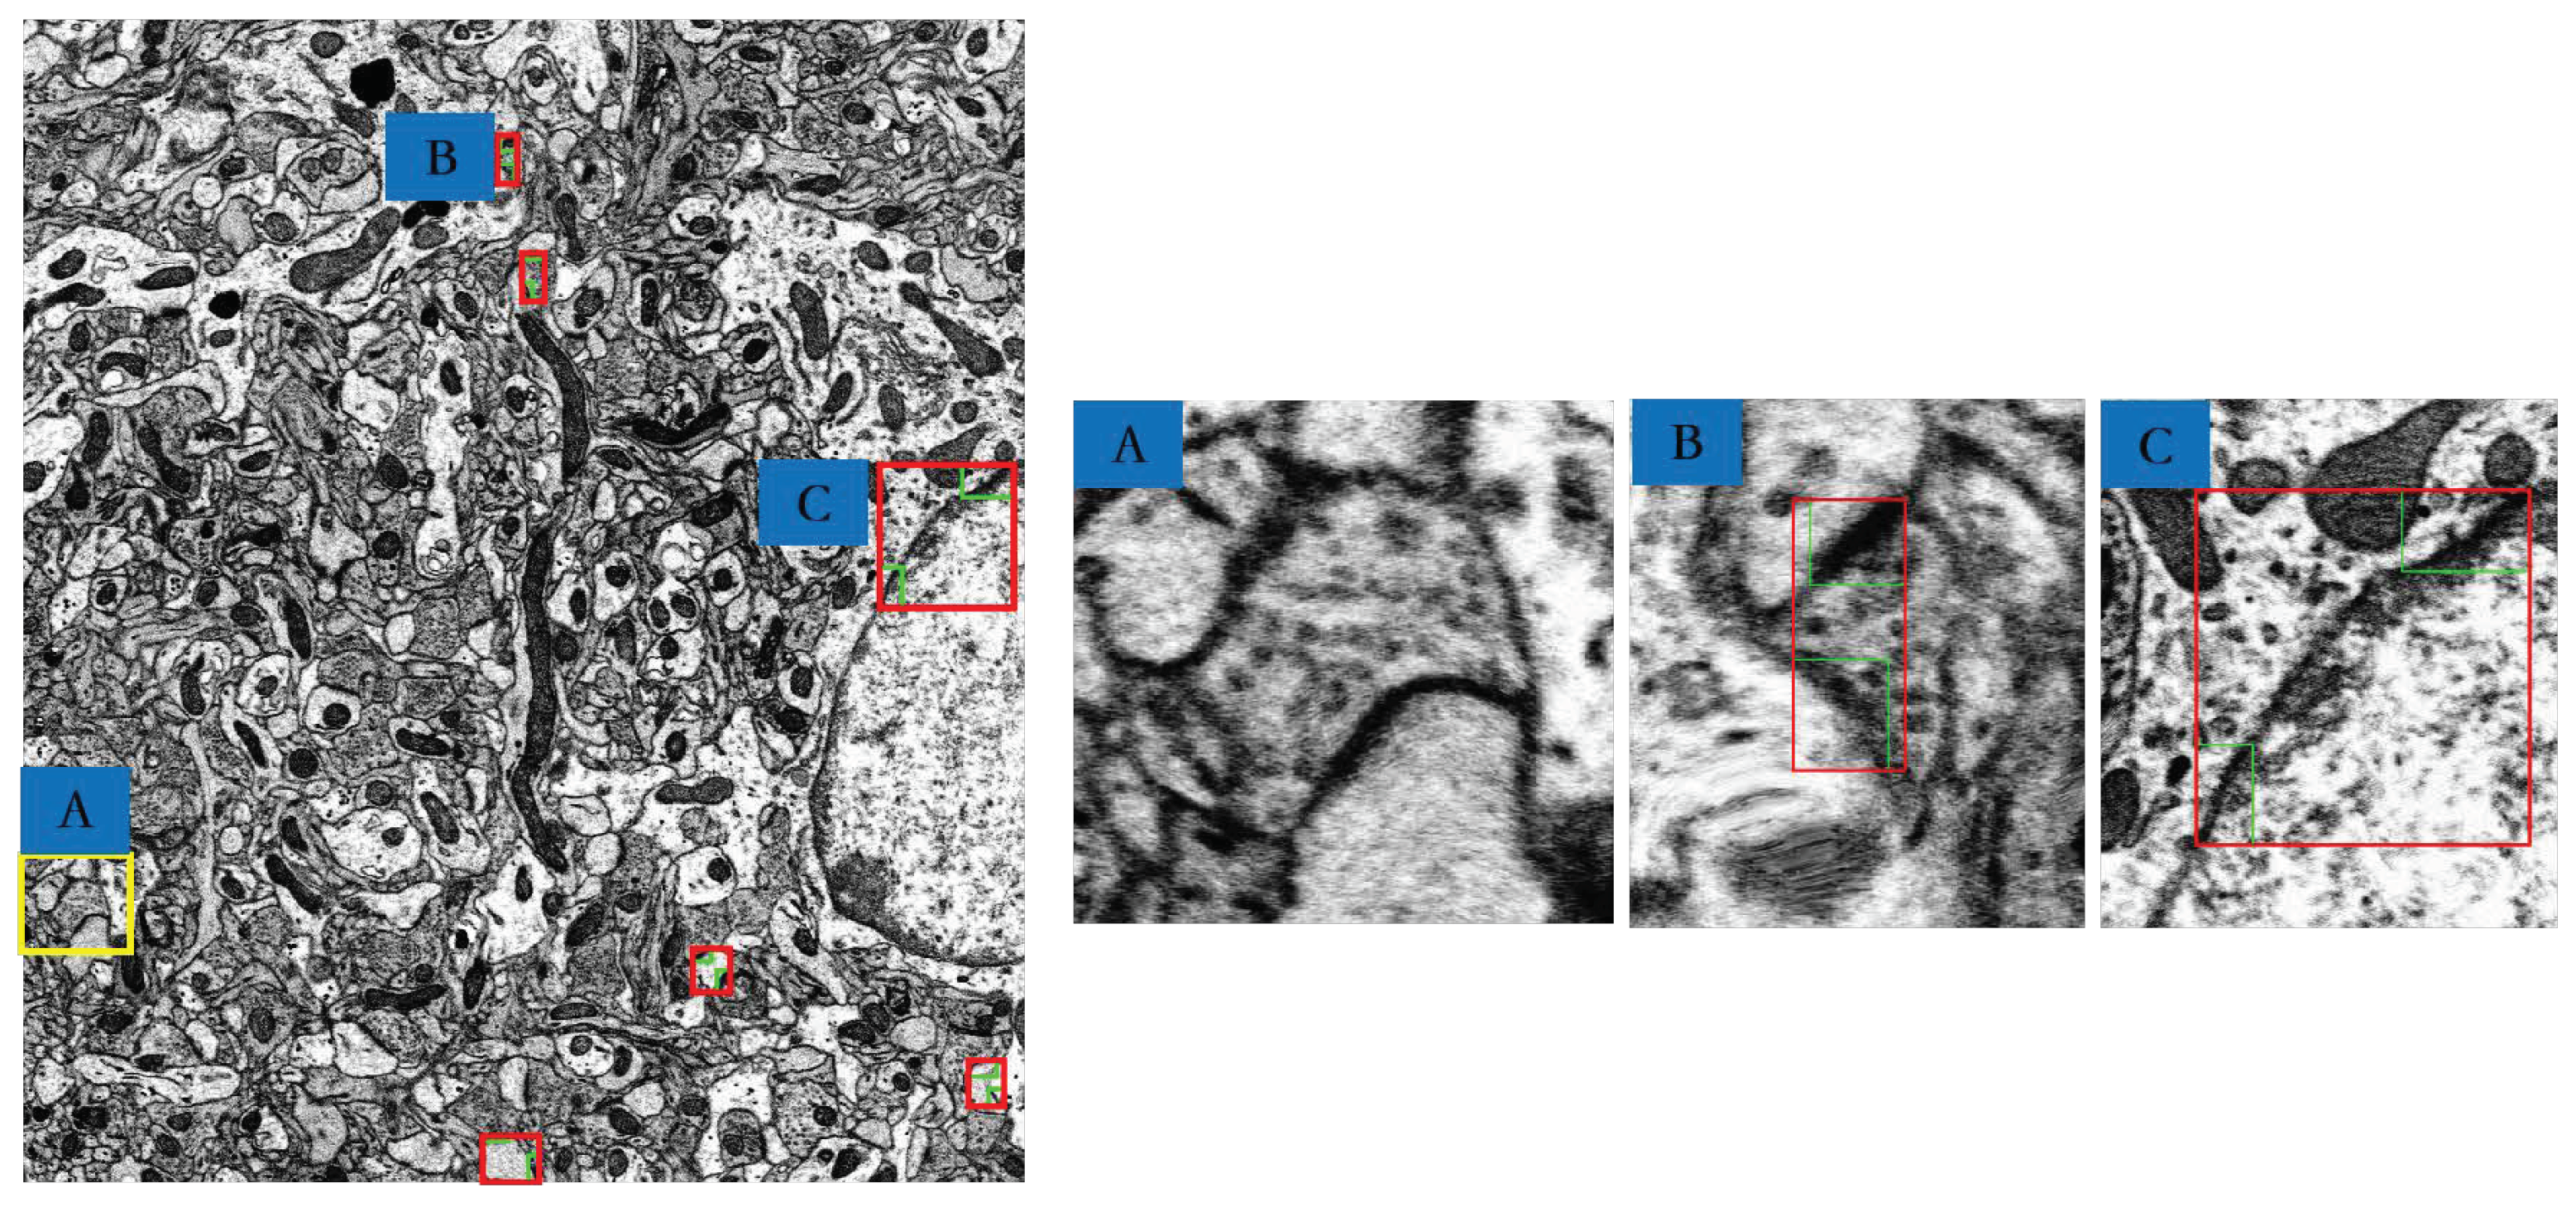

| J(Synapses, Ground truth) | Area(Neuron) (µm2) | Area(Synapse) (µm2) | Area(Neuron)/Area(Synapses) | |

|---|---|---|---|---|

| A | 62.54% | 0.2050 | 0.0266 | 12.98% |

| B | 57.48% | 0.3634 | 0.0334 | 9.20% |

| C | 48.40% | 0.6497 | 0.0048 | 7.40% |

| Type A | Type B | Type C | Total | |

|---|---|---|---|---|

| Numbers | 946 | 50 | 7 | 1003 |

| Ratio | 94.31% | 4.99% | 0.7% | 100% |